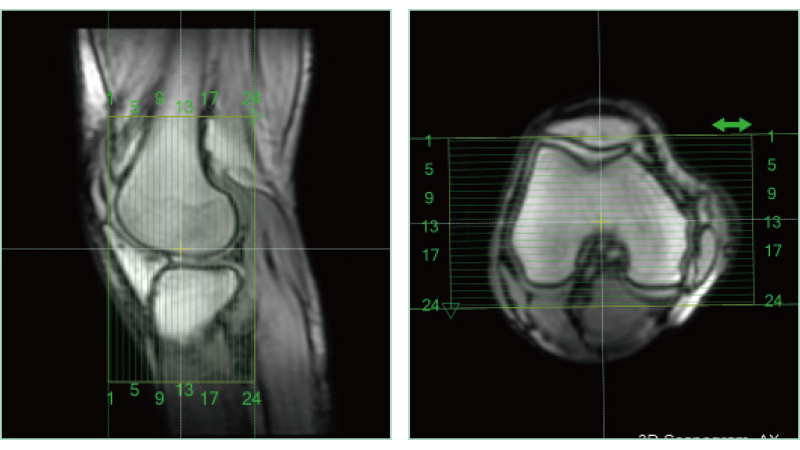

AutoPose Joelho

A função de suporte à configuração da linha de corte, "AutoPose", define automaticamente as linhas de corte assim que o escanograma é digitalizado.